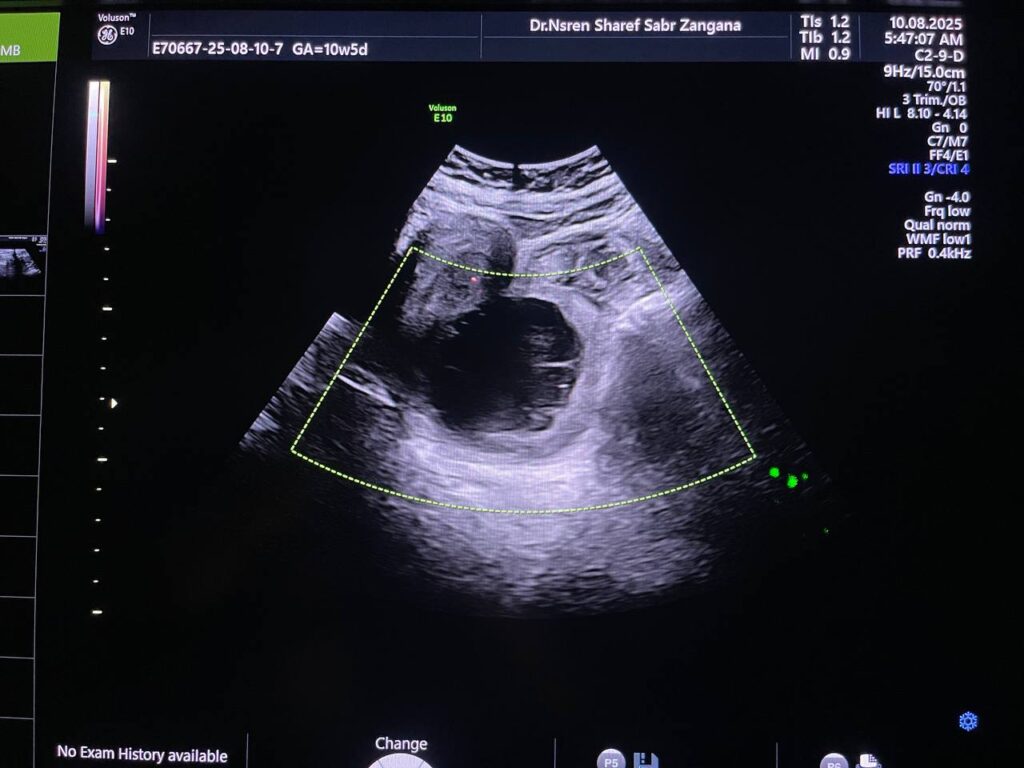

Right ovarian heterogeneous circumscribed avascular cystic mass its size 55x55mm, mostly hemorrhagic , with whirlpool sign , picture mostly of Twisted right hemorrhagic ovarian cystic , Cystic TORSION , please for further study ??

· No free pelvic fluid seen